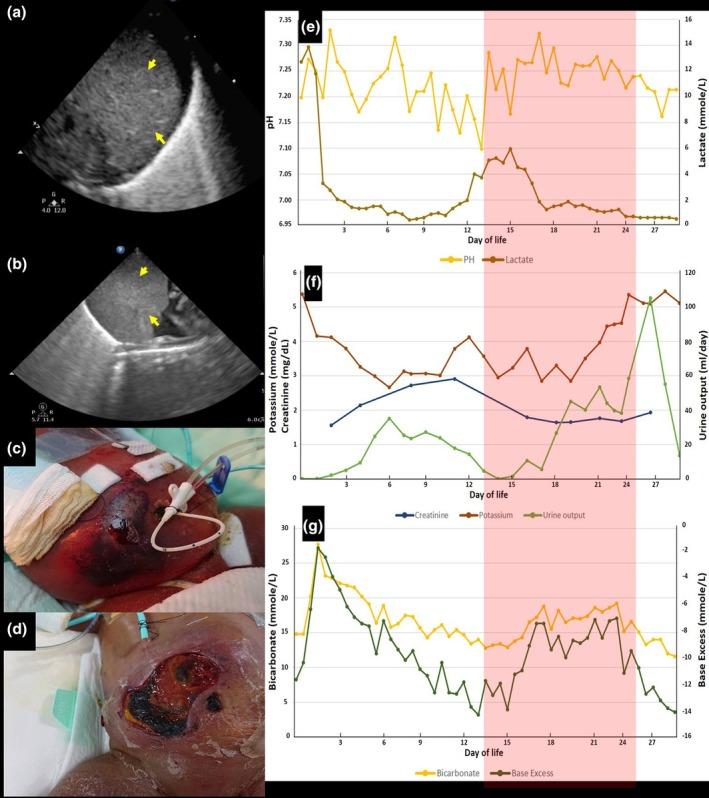

Peritoneal dialysis in an ELBW infant after resolution of hemoperitoneum: Challenges with peritonitis and cellulitis.

https://cdn.ncbi.nlm.nih.gov/pmc/blobs/2e6d/12215212/0a82f62292a9/PED-67-e70128-g001.jpg